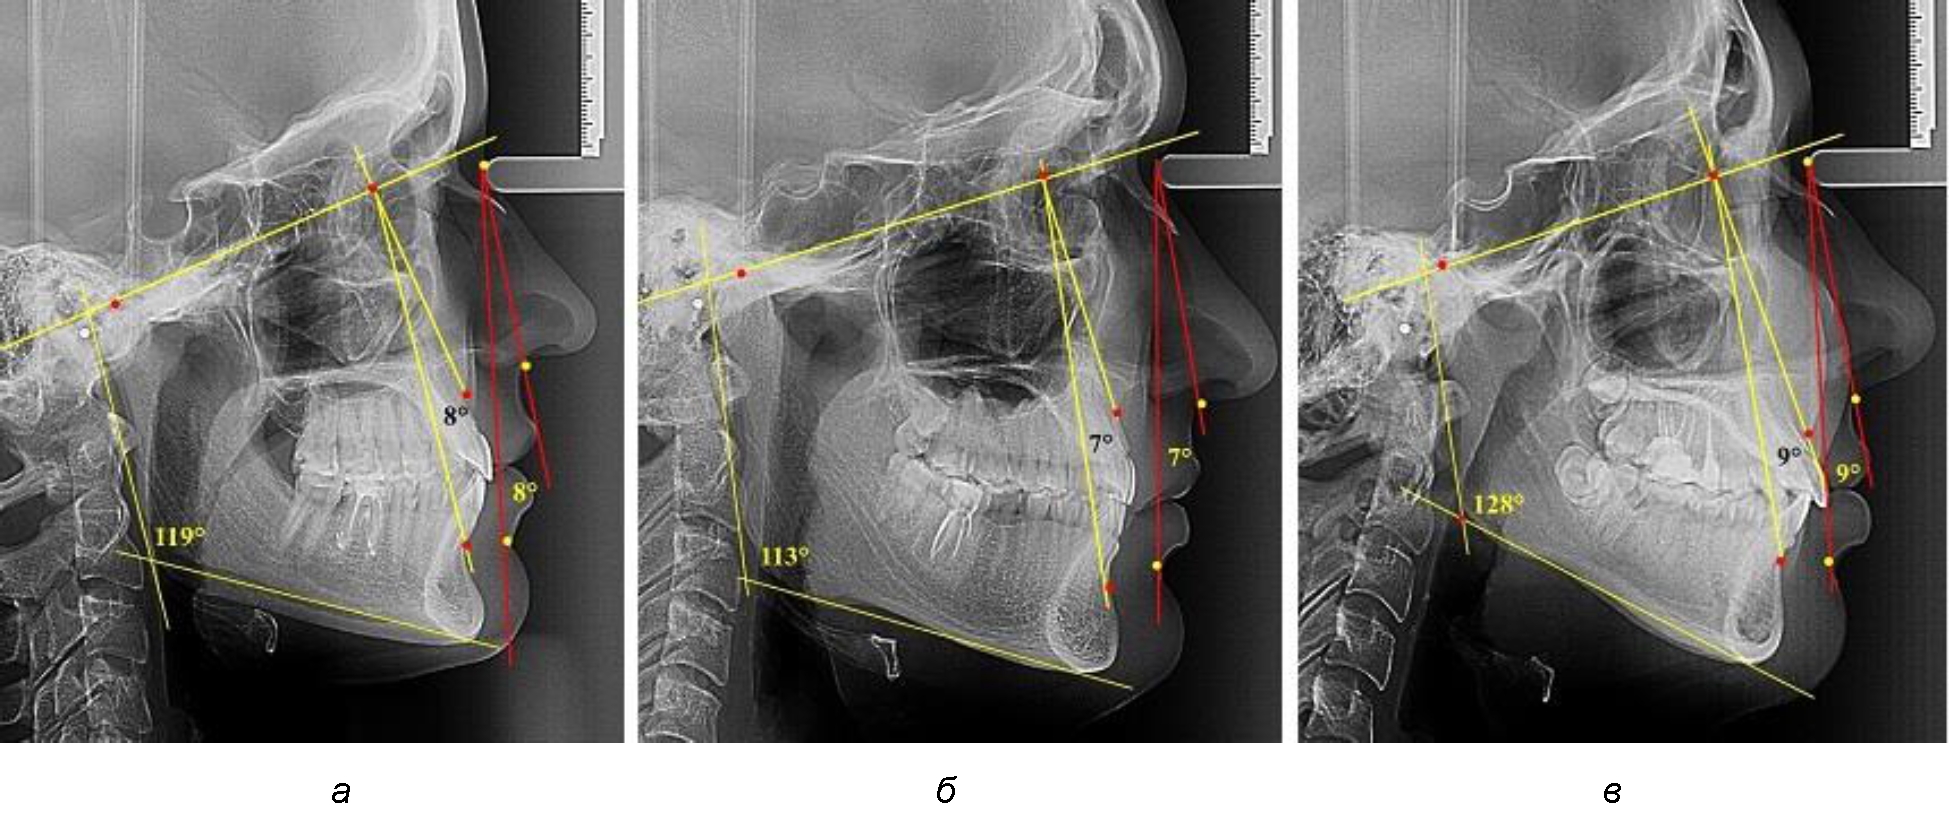

В группе людей с нейтральным типом нижнечелюстного угла величина лицевого межгнатического угла составляла (7,98 ± 0,49)° при использовании как кожных, так и костных ориентиров (рис. 3).

Рис. 3. Параметры кожного и костного лицевого межгнатического угла при нейтральном (а), горизонтальном (б) и вертикальном в типах угла нижней челюсти

В группе людей с горизонтальным типом нижнечелюстного угла величина лицевого межгнатического угла была несколько меньше и составляла (7,05 ± 0,37)° при использовании как кожных, так и костных ориентиров.

В группе людей с вертикальным типом нижнечелюстного угла величина лицевого межгнатического угла была больше, чем при других типах и составляла (9,23 ± 0,45)° при использовании как кожных, так и костных ориентиров. Таким образом, при всех типах нижнечелюстного угла отмечалось равенство параметров лицевого межгнатического угла как по кожным, так и по костным ориентирам. Полученные сведения легли в основу определения лицевого межгнатического угла на фотографиях в профиль при различных позиционных типах лица.

При оценке параметров лицевого межгнатического угла при аномалиях окклюзии учитывали патологии, классифицированные Энглем. При аномалиях окклюзии I класса величина исследуемого угла была близка к показателям, полученным у людей с физиологической нормой окклюзионных соотношений, что свидетельствует о зубоальвеолярной форме патологии и оптимальном расположении челюстей в структуре лицевого комплекса (рис. 5).

Рис. 5. Параметры лицевого межгнатического угла при аномалиях окклюзии I класса (а), II класса (б) и III класса (в)

Для аномалий окклюзии II класса Энгля было характерно увеличение угла более 11°, и оно зависело от степени дистального смещения нижней челюсти.

Для аномалий окклюзии III класса характерно уменьшение угла менее 5° вплоть до отрицательных значений.